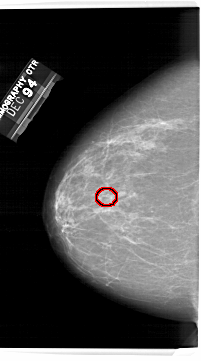

A_1245_1.LEFT_MLO

LEFT_MLO LINES 6346 PIXELS_PER_LINE 3796 BITS_PER_PIXEL 12 RESOLUTION 43.5 OVERLAY

FILE: A_1245_1.LEFT_MLO.OVERLAY

TOTAL_ABNORMALITIES 1

ABNORMALITY 1

LESION_TYPE CALCIFICATION TYPE PLEOMORPHIC DISTRIBUTION CLUSTERED

ASSESSMENT 4

SUBTLETY 4

PATHOLOGY MALIGNANT

TOTAL_OUTLINES 1

BOUNDARY